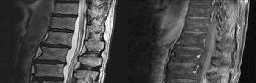

Figures 1 and 2 show sagittal and axial MRI from an 83-year-old woman with an ataxic gait, loss of dexterity, and intermittent loss of bowel and bladder control. The symptoms have been getting progressively worse over the past several weeks.

What disease process is most likely the cause of the patient’s symptoms?

4. Pigmented villonodular synovitis Discussion: B

The patient has a pannus at the C1-2 articulation that is compressing the spinal cord and causing myelopathy symptoms. The development of a pannus at this location has been associated with rheumatoid arthritis. Steinberger and associates showed increased morbidity and mortality when using an anterior approach and the surgery took longer than 4 hours. Chieng and associates showed better outcomes and lower complications rates using a posterior approach.